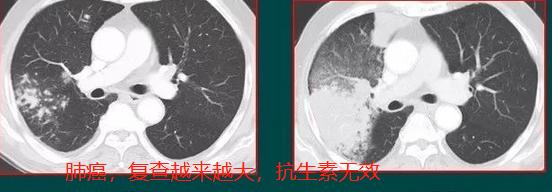

抗炎治疗无效,病灶逐渐增大,肺癌

上面3个病例都是确诊的肺癌,第1和第3例还有手术切除的机会,第2例是转移性癌,没有手术机会了,只能保守治疗。